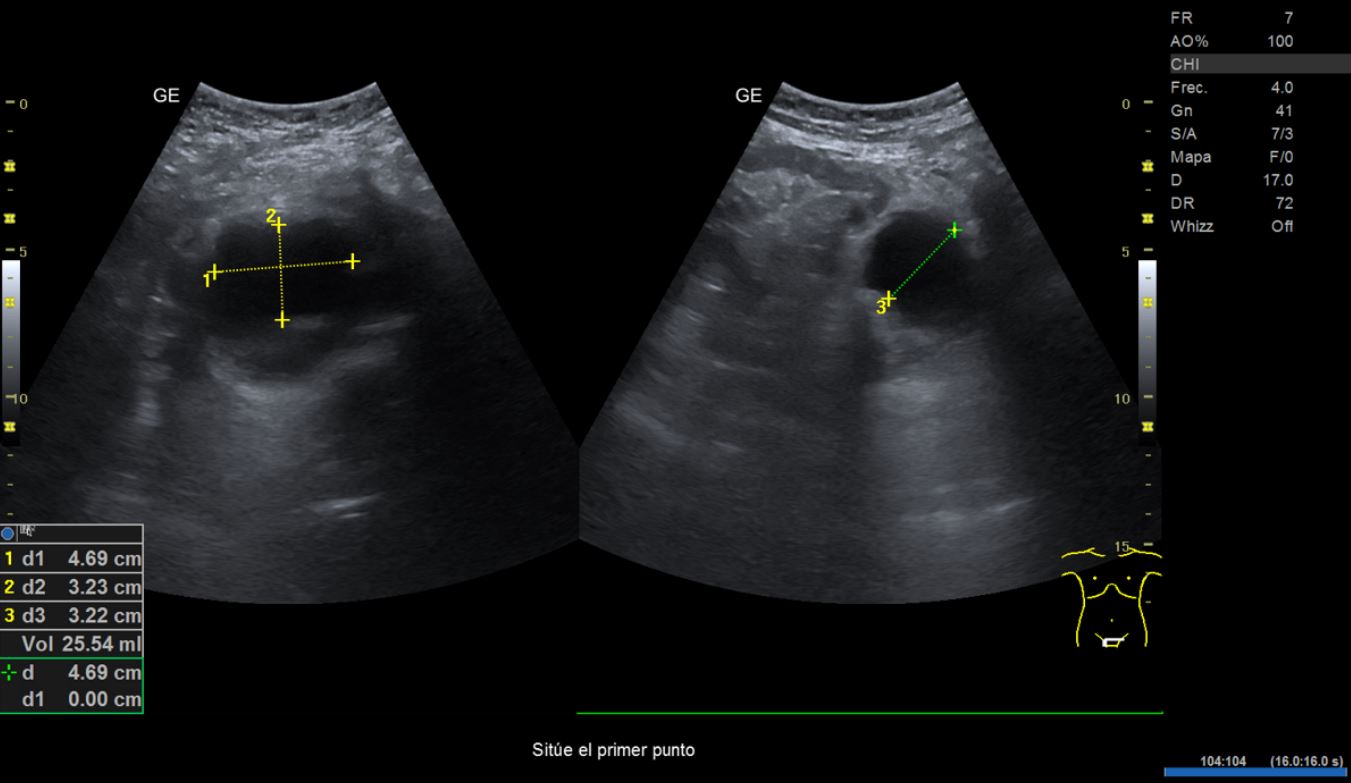

• Ecografía clínica renovesical: riñones con diámetro dentro de la normalidad. Relación cortico-medular normal. Pedículo renal Doppler normal. No se observan litiasis. Vejiga repleta, paredes finas, se observa imagen hipoecogénica en pared posterior lateral derecha que no capta señal Doppler, de unos 2,21 cm de diámetro aproximadamente. Volumen premiccional 290,86 ml, volumen posmiccional 25,54 ml.